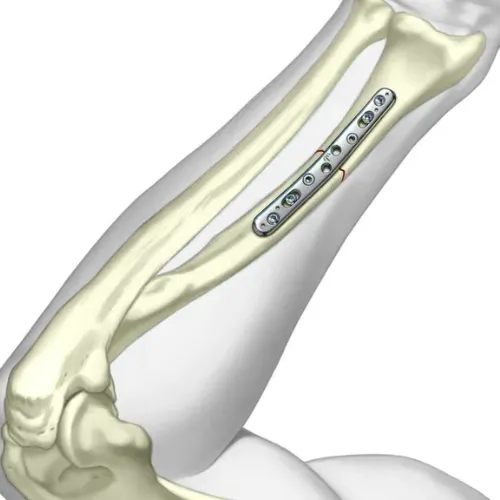

Forearm plating surgery is an orthopedic procedure used to treat fractures of the radius, ulna, or both bones in the forearm. Metal plates and screws are surgically fixed to the bone to provide stability, ensure proper alignment, and allow the bone to heal correctly. This procedure is commonly performed in displaced, unstable, or complex fractures where casting alone is insufficient.

The surgeon makes a small incision over the fractured bone, gently exposes the fracture site, and realigns the bone fragments into their correct anatomical position. Stainless steel or titanium plates are then fixed using screws to stabilize the bone securely.

In cases of both-bone forearm fractures, each bone is individually plated using separateincisions. This ensures better stability, quicker healing, and prevents long-term deformity or arm weakness.